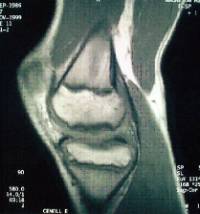

És una patologia ocasionada per una isquèmia transitòria de l’os subcondral i pot progressar fins a arribar a desprendre’s.

Es localitza amb més freqüència al còndil femoral intern i el seu pronòstic varia en funció de l’edat de presentació (poc freqüent per sota dels 10 anys) i l’estabilitat de la lesió.

El tractament passa per limitar l’activitat esportiva d’impacte, variar l’eix de càrrega mecànic de l’extremitat i, potser, dur a terme una intervenció quirúrgica.

Hi ha diferents opcions de tractament quirúrgic en funció de l’estabilitat i localització del fragment osteocondral (microperforacions sota control artroscòpic, fixació in situ del fragment osteocondral, ús d’empelts osteocondrals/mosaicoplàstia).

En els casos evolucionats amb despreniment del fragment osteocondral, cal retirar el cos lliure articular ("ratolí" articular).